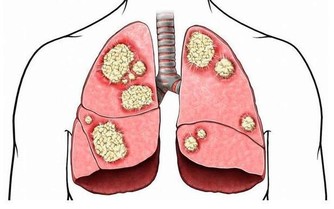

三、提高患癌風險

熬夜會讓內分泌激素水平紊亂,使得細胞代謝異常,影響人體細胞正常分裂,導致細胞突變,提高四、患癌風險。